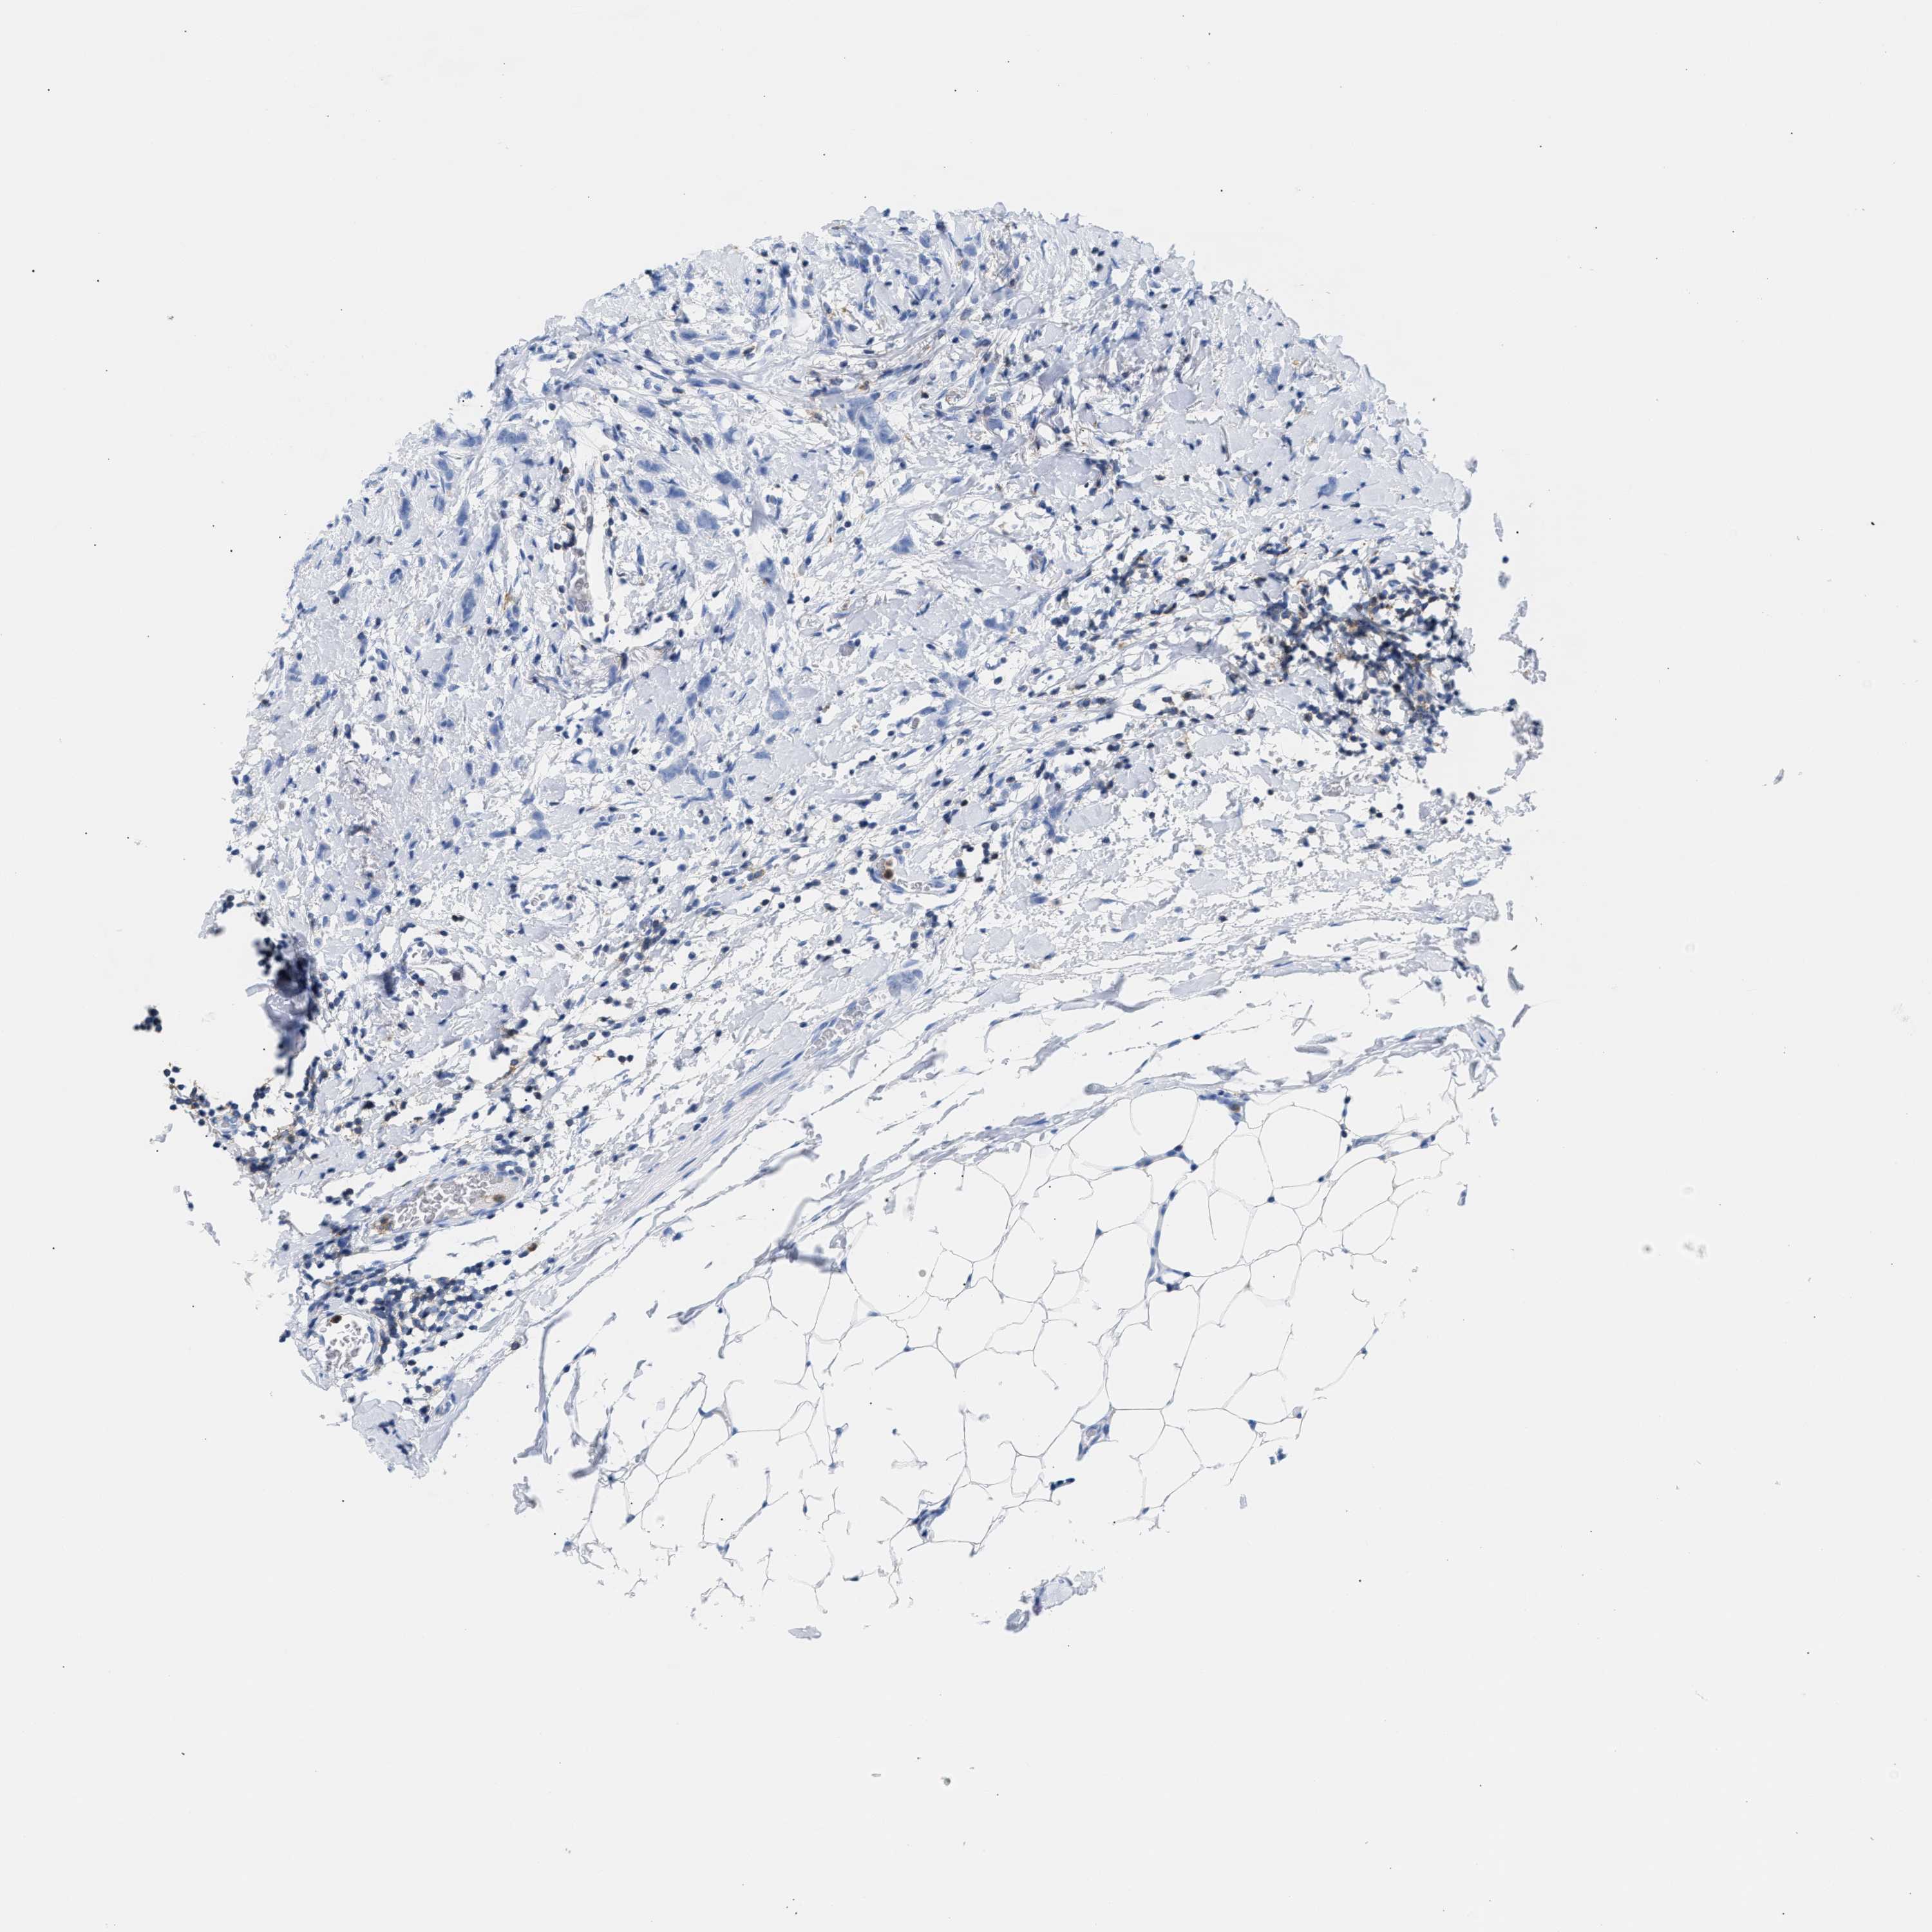

CANCER BREAST CANCER Show tissue menu

BRCA TCGA BRCA VALIDATION PROTEIN EXPRESSION

ANTIBODIES

AND

VALIDATION